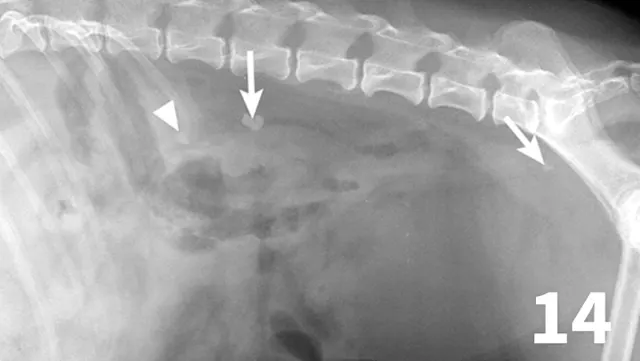

Normal ureters cannot be visualized with survey radiography or ultrasonography, but normal and abnormal ureters are readily visualized with excretory urography. The location of a ureteral obstruction or rupture as well as the presence of an ectopic ureter (especially when combined with pneumocystography) can be documented with excretory urography (Figure 11). A dilated ureter (hydroureter) can be observed with ultrasonography (Figure 12). Pyelocentesis (for cytology and culture) and antegrade pyelography (nephropyelography) (Figure 13) to document obstruction or leakage can be conducted via ultrasound guidance with heavy sedation or anesthesia. Ultrasonography can also be used to visualize retroperitoneal fluid accumulation, which may occur with a ureteral rupture, hemorrhage, or infectious or neoplastic disease. Whereas ureteroliths without hydroureter may be missed on ultrasonography, radiopaque ureteroliths can be observed on survey radiography (Figure 14). Survey radiographic visualization of radiopaque ureteroliths may be facilitated by enemas to empty the colon of fecal material and/or use of a radiolucent paddle to apply regional compression over the ureter to separate adjacent organs (eg, loops of bowel) (Figure 15). Aged cats with chronic kidney disease (CKD) frequently have calcium oxalate nephroliths; in some cases, these nephroliths will migrate into the ureters. Survey radiographs should be employed to rule out ureterolithiasis, especially in cats with acute decompensation of their CKD (Figure 16).